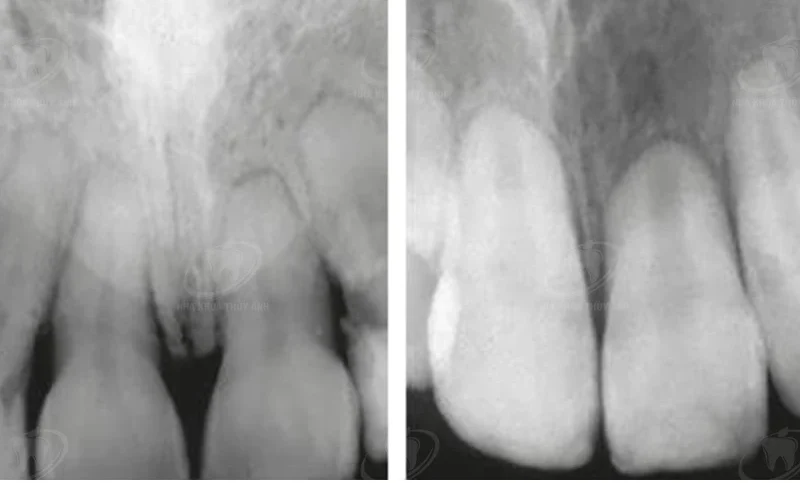

Nanh sữa hay gặp ở trẻ sơ sinh từ 0 – 3 tháng tuổi, một số trường hợp gặp muộn hơn nhưng hiếm khi gặp trên 8 tháng tuổi, và nó xuất hiện ở hơn một nửa số trẻ mới sinh. Tuy nhiên tỷ lệ thực tế có thể còn cao hơn nữa do đây là một tổn thương lành tính, xuất hiện trong thời gian ngắn, ít khi gây đau đớn cho trẻ và thường tự vỡ rồi biến mất trong khoảng 2 tuần do vậy thường được bỏ qua không đến khám ở cơ sở y tế. Trường hợp nang to có thể tồn tại đến 5 tháng mà không gây biến chứng gì. Không chỉ gặp ở lợi, nanh sữa còn có thể thấy ở niêm mạc vòm miệng, nhưng cũng như ở lợi, chúng thường tự vỡ và tan biến mà không để lại dấu vết. Bản chất của nanh sữa là một loại nang có vỏ mỏng trong lòng chứa đầy chất keratin (một sản phẩm thoái hóa của biểu mô sừng hóa) màu trắng do các mảnh vụn tế bào trong quá trình hình thành răng sữa còn sót lại ở xương hàm, nếu là nanh sữa ở vòm miệng thì do mảnh vụn của các tế bào tuyến nước bọt phụ bị vùi kẹt dưới niêm mạc trong thời kỳ bào thai. Răng sữa thường mọc lúc trẻ được 5 – 6 tháng tuổi, tuy nhiên mầm răng thì đã được hình thành trong xương từ lúc trẻ vẫn còn trong bụng mẹ, và trong quá trình hình thành mầm răng một số thành phần tế bào (trong đó có biểu mô lá răng) tham gia tạo răng đáng lẽ phải tiêu biến, nếu còn sót lại sẽ có thể tạo thành nang. Đa số trường hợp nanh sữa không gây đau đớn hay khó chịu gì nhiều cho trẻ. Tuy nhiên, cũng có trẻ quấy khóc hoặc bỏ bú, những trường hợp này là do nanh sữa bị nhiễm khuẩn gây sưng đau khi chạm phải. Khi bị nhiễm khuẩn, nanh vẫn có màu trắng nhưng niêm mạc lợi xung quanh rìa đốm trắng sẽ có màu đỏ, sưng thậm chí còn bị loét do sang chấn, có thể có sốt nhẹ. Rất dễ phát hiện Nanh sữa dễ được phát hiện và chẩn đoán, tuy nhiên có trường hợp hiếm, dễ nhầm nanh sữa với răng bẩm sinh hoặc răng sơ sinh (natal và neonatal teeth ) mọc ngay sau khi sinh đã có (natal teeth) hoặc mọc trong vòng 30 ngày sau sinh. Tỷ lệ gặp những răng này rất hiếm, hay gặp ở vị trí hai răng cửa giữa hàm dưới.

Đây có thể là những răng sữa thật sự chỉ có điều chưa hoàn chỉnh về cấu trúc và chân răng rất ngắn nên dễ lung lay và dễ nhổ hoặc có thể là các răng thừa chưa hoàn thiện các cấu trúc. Phần lớn trường hợp này cũng phải cho trẻ đi nhổ răng để tránh tổn thương lưỡi cho trẻ, gây đau cho mẹ khi bú hoặc do răng lung lay nhiều có thể tự rụng gây nguy hiểm cho đường hô hấp trên.